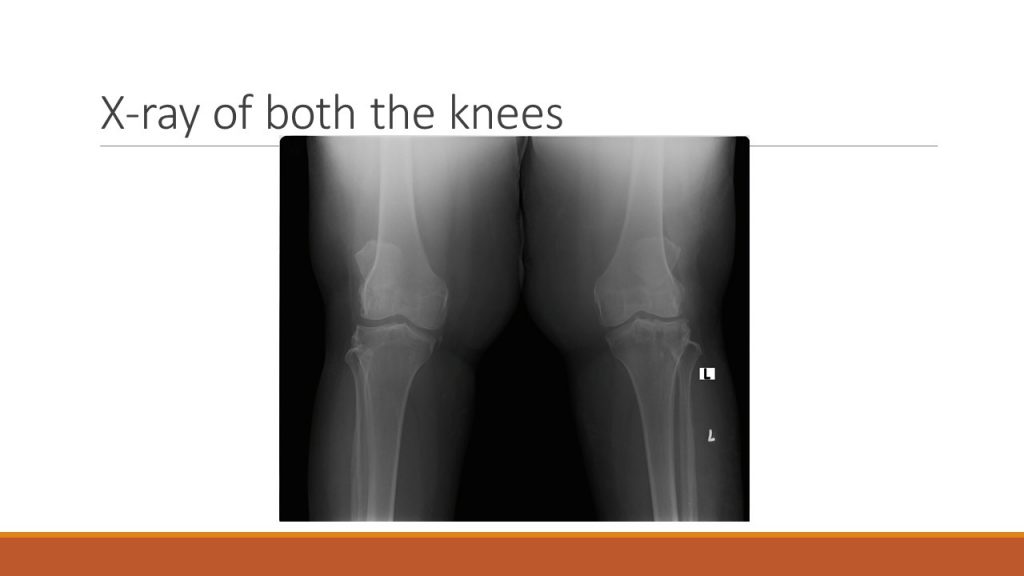

X-ray of both the knees

X-ray of both knees indicates